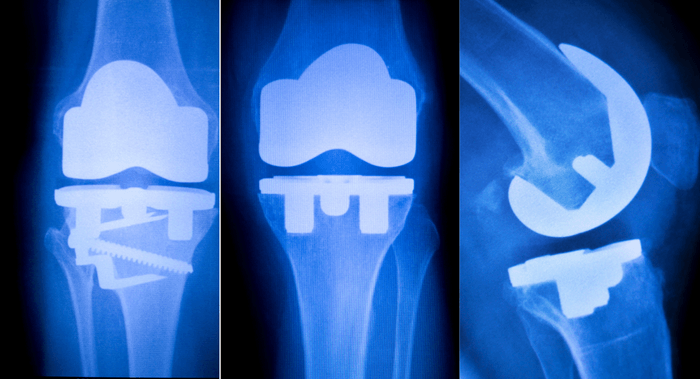

Report Oceanが発行した最新レポートによると、整形外科用インプラントの世界市場は、2025年までに65億5,832万米ドルに達すると予測されています。2017年、アプリケーションタイプでは、膝の整形外科用インプラントセグメントが収益面で最大の市場シェアを占めています。地域別では、北米が整形外科用インプラント市場の主要なシェアを占めています。

世界の整形外科用インプラント市場は、アプリケーションタイプ別に、脊椎整形外科用インプラント、股関節整形外科用インプラント、膝整形外科用インプラント、頭蓋顎顔面整形外科用インプラント、歯科用整形外科用インプラント、S.E.T(Sports Medicine, Extremities, Trauma)整形外科用インプラントに分類されています。